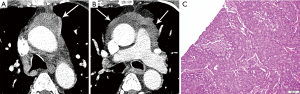

The hallmark of the histological diagnosis of thymoma is the presence of two cell populations, one comprised of epithelial cells and another of immature lymphocytes (Figure 4). However, this classic feature may not be present in many cases due to sampling and histological variation. Immunohistochemical (IHC) stains are very helpful as the thymocyte epithelial cells are positive for keratin, whereas immature lymphocytes are positive for TdT. There must be close co-localization of the two cell populations, as the markers individually are not specific for the diagnosis of thymoma and can be seen in other entities. As an example, TdT positive lymphocytes are present in acute lymphoblastic lymphoma, a common lymphoproliferative disorder of the mediastinum in children and younger adults. The immature (TdT positive) lymphocytes are also seen in metastatic thymoma, a useful diagnostic feature for the diagnosis of thymoma outside of the mediastinum.

The histological diagnosis of thymic hyperplasia and thymoma is very difficult to render in a biopsy specimen due to overlapping characteristics (dual population of bland epithelial cells and immature lymphocytes). The differentiation of thymic hyperplasia from thymoma is best made on excisional biopsy. Thymic hyperplasia maintains the normal organotypic organization of the thymus, which is lost in thymoma. Resection of thymic hyperplasia is indicated in cases of Myasthenia gravis.